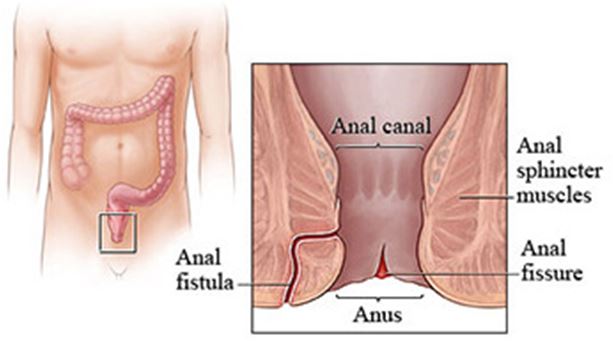

Overview

Package includes:

Days in hospital : 2 to 3 Days (For patient and one attendant)

Days in hotel : 7 Days (For patient and one attendant)

Room type in hospital : Shared

Room type in hotel : Private

Hotel category: Standard

Value added benefits of the Anal Fitsula: